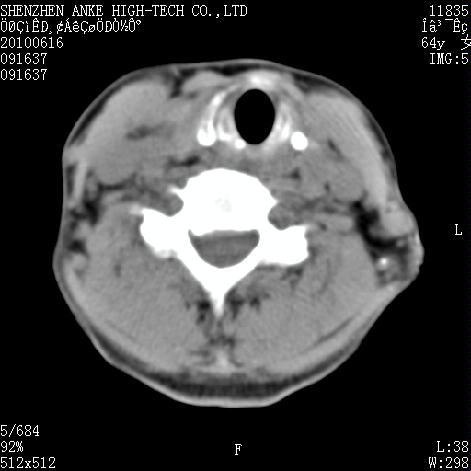

标题: CT27132:患者女,64岁,颈部及全身多处包块,现觉吞咽困难4 [打印本页]

标题: CT27132:患者女,64岁,颈部及全身多处包块,现觉吞咽困难4

右侧甲状腺占位,肿瘤可能性大,癌

右侧甲状腺癌伴右颌下腺淋巴结转移

右侧甲状腺癌伴淋巴结转移

右侧甲状腺癌伴淋巴结转移可能性大